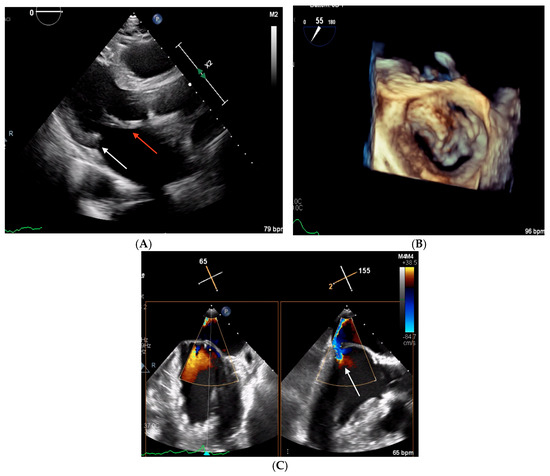

2.2. Clinical Case 2